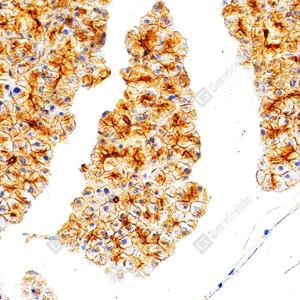

IHC检测Cytokeratin 18蛋白(货号 GB15232). 样品: 人肺癌, 4%多聚甲醛 (货号G1101) 固定12-24小时. 抗原修复: 柠檬酸抗原修复液(干粉, pH 6.0) (G1201), 高压锅均匀喷气计时2分钟. —抗: 1: 500稀释, 4℃ 孵育过夜. 二抗: S-vision免疫组化多聚二抗(山羊抗小鼠), 即用型(货号G1301), 室温孵育20分钟. |